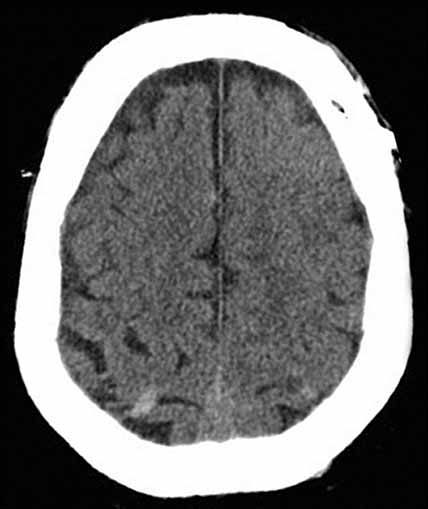

Loss of Consciousness in a 50-yr-old Man

The patient is sent for head CT, and the scan is shown. Which is the following is a correct interpretation of this CT scan? (Please choose only one answer.)